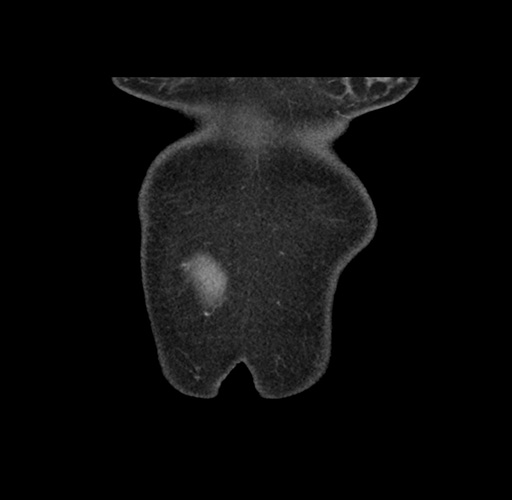

Imaging Analysis

Look through the patient's CT scan to identify any areas of concern for the necessary procedure.

Based on your CT findings, which issue(s) would give reason for "planned slowing down moment(s)" in this case?

Considering a standard left lateral sectionectomy procedure, what step(s) of the operation would you do differently in this case ?